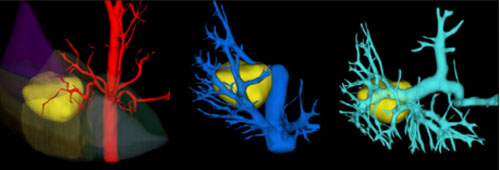

CT磁共振科应用的“人工智能手术规划”系统,通过AI图像处理算法技术,基于CT平扫和CT增强图像进行精准3D三维重建,能够为临床提供全面的解剖结构与病灶信息,帮助医生从任意角度观察、分析病灶,更好地制定手术规划,为术前精确诊断病情、术中精准切除病灶、术后患者快速康复提供了更全面的支持保障。

肝胆外科收治的这名患者主因皮肤黄染伴腹部疼痛数月余,综合临床症状及检查检验结果,临床医生评估患者情况十分危急,若不及时进行手术会危及生命。CT磁共振科对患者实际情况精准进行了医学影像三维重建,彩色3D图像清晰显示了肝内各个分段及肝动静脉,以及肝内肿瘤的位置、大小及与周围肝内血管、肝内胆管的关系。

术中,肝胆外科医生对照彩色3D图像,仔细剥离病灶周围肝静脉、肝动脉及肝内胆管,切除包含病灶在内的“肝右叶+右尾状叶+肝门部胆管”,保留肝左叶及周围血管组织,同时规划系统对患者残肝比等关键指标进行了定量计算,为患者术后恢复治疗提供了重要参考数据。